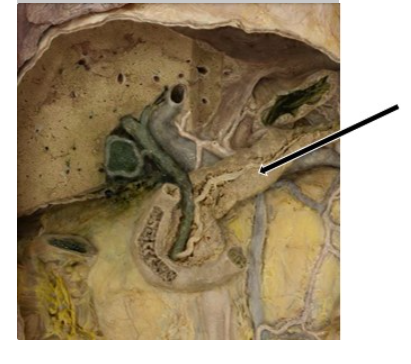

What is the organ indicated in the figure?

Pancreas

What duct is indicated in the figure?

Bile duct